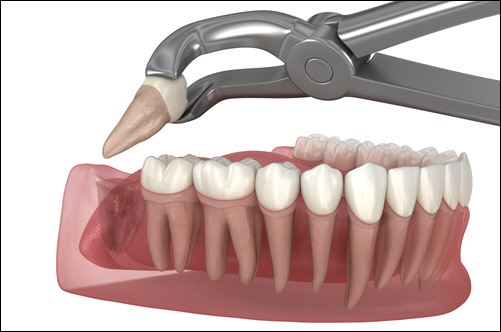

The Extraction Process

Wisdom teeth extraction typically takes about 45 minutes to an hour. After administering anesthesia to ensure you feel comfortable and pain-free, the dentist or oral surgeon begins the procedure. If the tooth is impacted, they may make a small incision in the gum and, if needed, gently remove the tooth in sections to minimize discomfort and ease the process.

You might feel pressure during the extraction, but the anesthesia will prevent you from feeling pain. Once the teeth are removed, the surgeon will clean the area and may use stitches to help the gums heal.